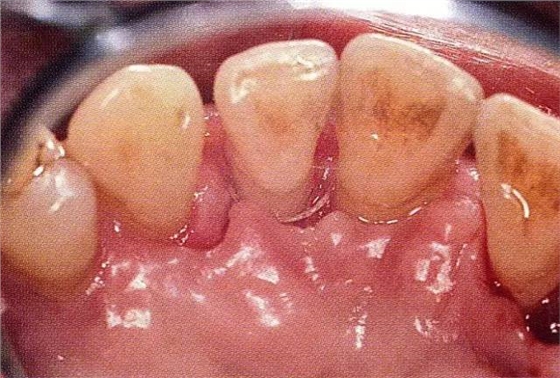

▲圖7-6再翻瓣半年之后的狀態(tài)。探診無出血,獲得了附著齦。